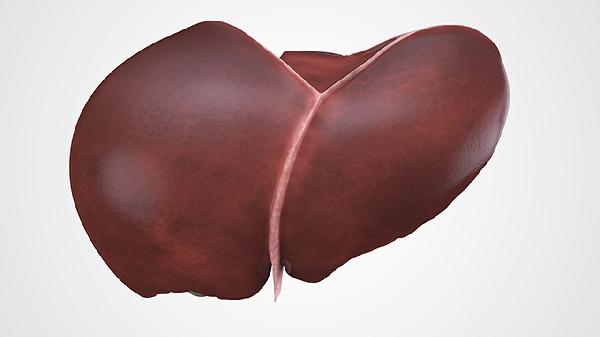

肾结石怎么形成

肾结石的形成可能与代谢异常、尿路梗阻、尿路感染、药物因素以及饮食因素等原因有关。

一、代谢异常

代谢异常是肾结石形成的常见原因之一。体内钙、草酸、尿酸等物质代谢紊乱,导致尿液中这些成分的浓度升高,从而析出结晶并逐渐聚集形成结石。高钙尿症、高草酸尿症等代谢疾病会使尿液中的成石物质过饱和,促进晶体形成和生长。患者可能出现腰部钝痛、血尿等症状。治疗时需针对原发代谢疾病进行干预,医生可能建议使用枸橼酸氢钾钠颗粒、别嘌醇片或氢氯噻嗪片等药物调节代谢,并配合饮食控制减少成石物质摄入。

二、尿路梗阻

尿路梗阻会导致尿液排出不畅,尿液在肾盂或输尿管内滞留,使得其中的矿物质浓度增加,易于结晶沉淀形成结石。梗阻可能由先天性输尿管狭窄、前列腺增生或肿瘤压迫等因素引起。患者常伴有肾积水、剧烈腰痛及排尿困难等症状。解除梗阻是治疗关键,医生会根据情况使用坦索罗辛胶囊、非那雄胺片等药物缓解症状,必要时通过手术去除梗阻原因,并鼓励患者增加水分摄入以稀释尿液。

三、尿路感染

尿路感染时某些细菌如变形杆菌能分解尿素产生氨,使尿液碱化,促进磷酸盐沉积形成感染性结石。反复感染会破坏尿路上皮,为晶体附着提供条件。患者可能出现发热、尿频、尿急及脓尿等表现。治疗需使用敏感抗生素如左氧氟沙星片、头孢克肟分散片或呋喃妥因肠溶片控制感染,同时多饮水冲刷尿道,减少细菌滋生。

四、药物因素

长期使用某些药物可能增加肾结石风险。例如过量服用维生素C补充剂可能增加尿草酸排泄,使用糖皮质激素可能影响钙代谢,某些抗HIV药物如茚地那韦也会诱发结晶形成。药物成分或其代谢产物在尿液中溶解度降低时易析出形成结石。患者服药期间可能出现无症状结晶尿或突发肾绞痛。建议在医生指导下调整用药方案,必要时换用替代药物,并定期监测尿液成分变化。

五、饮食因素

饮食中高嘌呤、高草酸或高钠食物摄入过多,同时水分摄入不足,会使尿液浓缩,成石物质浓度增高而促进结石形成。经常食用动物内脏、菠菜、巧克力等高草酸或高嘌呤食物,且每日饮水量不足,会增加尿酸结石或草酸钙结石概率。患者可能仅有轻微腰部不适或体检时偶然发现结石。调整饮食结构,限制成石食物摄入,增加水果蔬菜等碱性食物,保证每日充足饮水是有效的预防措施。

预防肾结石需要养成良好生活习惯,每日饮水至少2000毫升以保持尿液稀释,减少高草酸食物如菠菜、高嘌呤食物如海鲜摄入,适当控制钠盐和蛋白质摄入量。定期进行尿液检查和泌尿系统超声筛查,及时发现早期病变。保持适度运动有助于小结石排出,但应避免突然剧烈运动。出现疑似结石症状时应尽早就医检查,明确诊断后接受规范治疗。饮食调整结合医疗干预能有效降低结石复发风险。